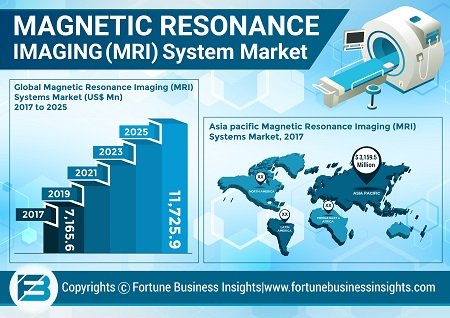

MRI System Emerging Techniques to Scale Higher Growth Rate

The advent of Superconducting Magnets and Software Upgrades to Boost Market

Using magnetic resonance imaging technique is considered as an effecti [...]